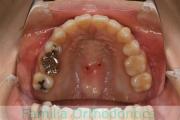

歯並びを治したいということで来院されました。下あごがやや右側に偏位して後退している、上顎前突(出っ歯)でした。上下左右から小臼歯を抜歯して、歯科矯正用アンカースクリューを併用したマルチブラケット法にて治療を行いました。約2年、24回の来院をしていただきました。

下顎の後退はいびきなどの上部気道の障害が出やすいと考えられます。